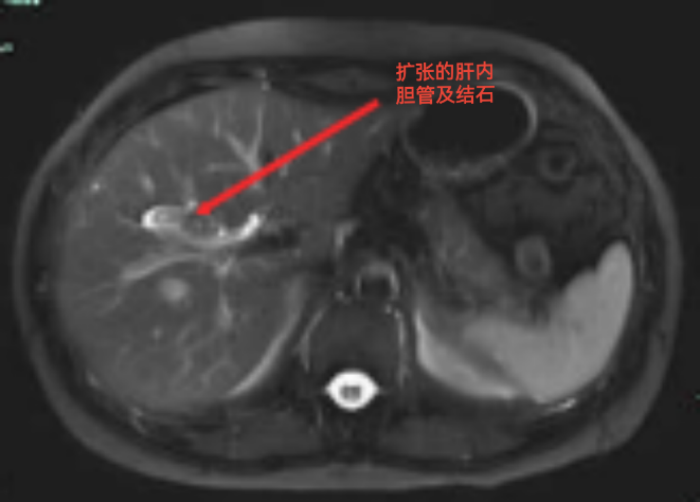

經(jīng)上腹部磁共振增強掃描,余女士被明確診斷為“膽囊結(jié)石;右肝內(nèi)膽管結(jié)石伴膽管擴張;右肝小囊腫?!?